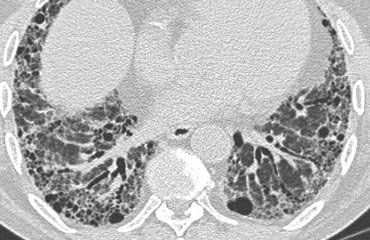

Crazy Paving

Refers to reticular opacificaties superimposed on areas of ground-glass opacity.

DDx:

Remember the “Ps”